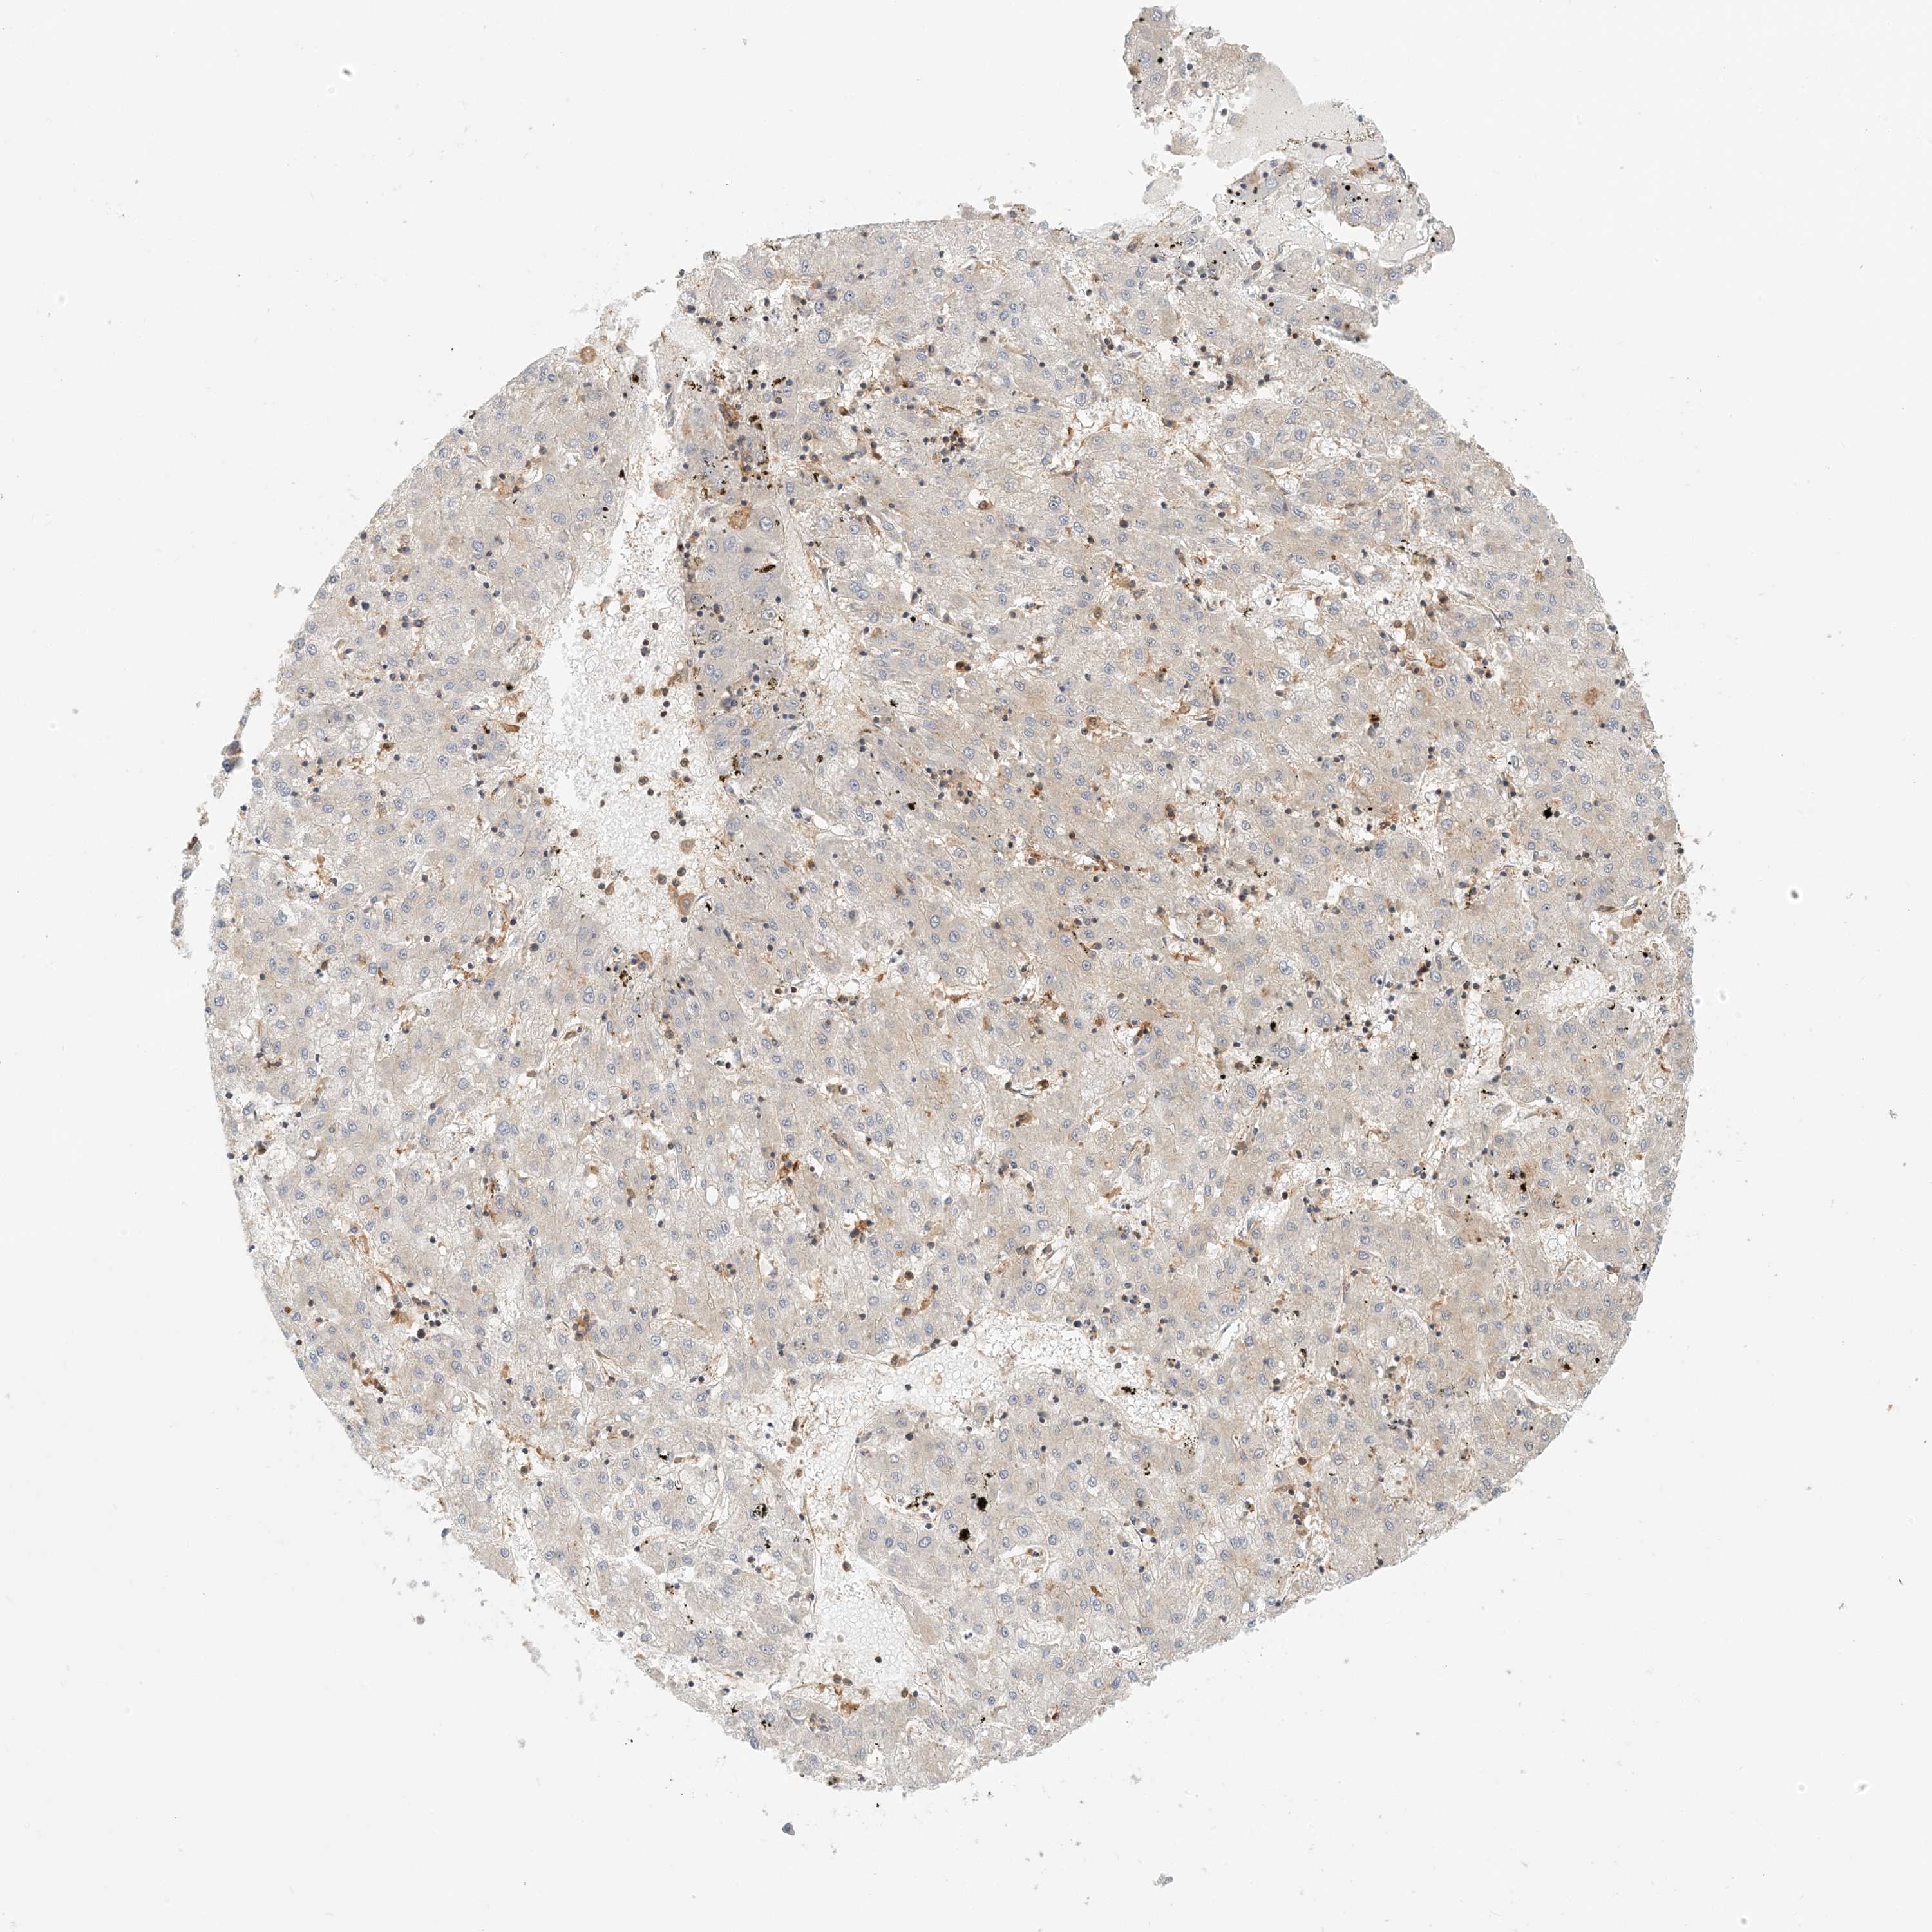

LIVER CANCER - Protein expressioni

A mouse-over function shows sample information and annotation data. Click on an image to view it in a full screen mode. Samples can be filtered based on level of antibody staining by selecting one or several of the following categories: high, medium, low and not detected. The assay and annotation is described here.

Note that samples used for immunohistochemistry by the Human Protein Atlas do not correspond to samples in the TCGA dataset.

Antibody stainingi

Antibody staining in the annotated cell types in the current human tissue is reported as not detected, low, medium, or high, based on conventional immunohistochemistry profiling in selected tissues. This score is based on the combination of the staining intensity and fraction of stained cells.

Each image is clickable and will lead to virtual microscopy that enables deeper exploration of all samples and also displays staining intensity scores, fraction scores and subcellular localization as well as patient and tissue information for each sample.

Antibody HPA035241

Staining

High

Medium

Low

Not detected

Intensity

Strong

Moderate

Weak

Negative

Quantity

>75%

75%-25%

<25%

None

Location

Nuclear

Cytoplasmic/membranous

Cytoplasmic/membranous,nuclear

Cholangiocarcinoma

Carcinoma, Hepatocellular, NOS